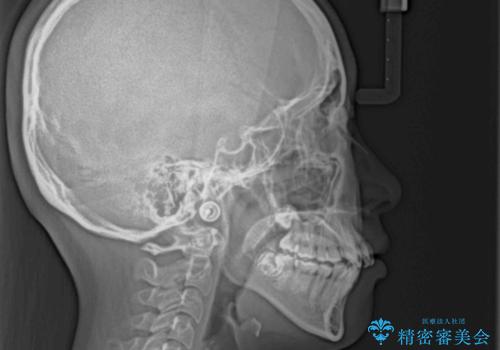

- 上下前歯の八重歯やデコボコと、唇の閉じにくさを気にして来院された患者様です。

口元の突出感を改善するため、上下左右の第一小臼歯4本を抜歯し、ワイヤー装置にて矯正治療を行うこととしました。